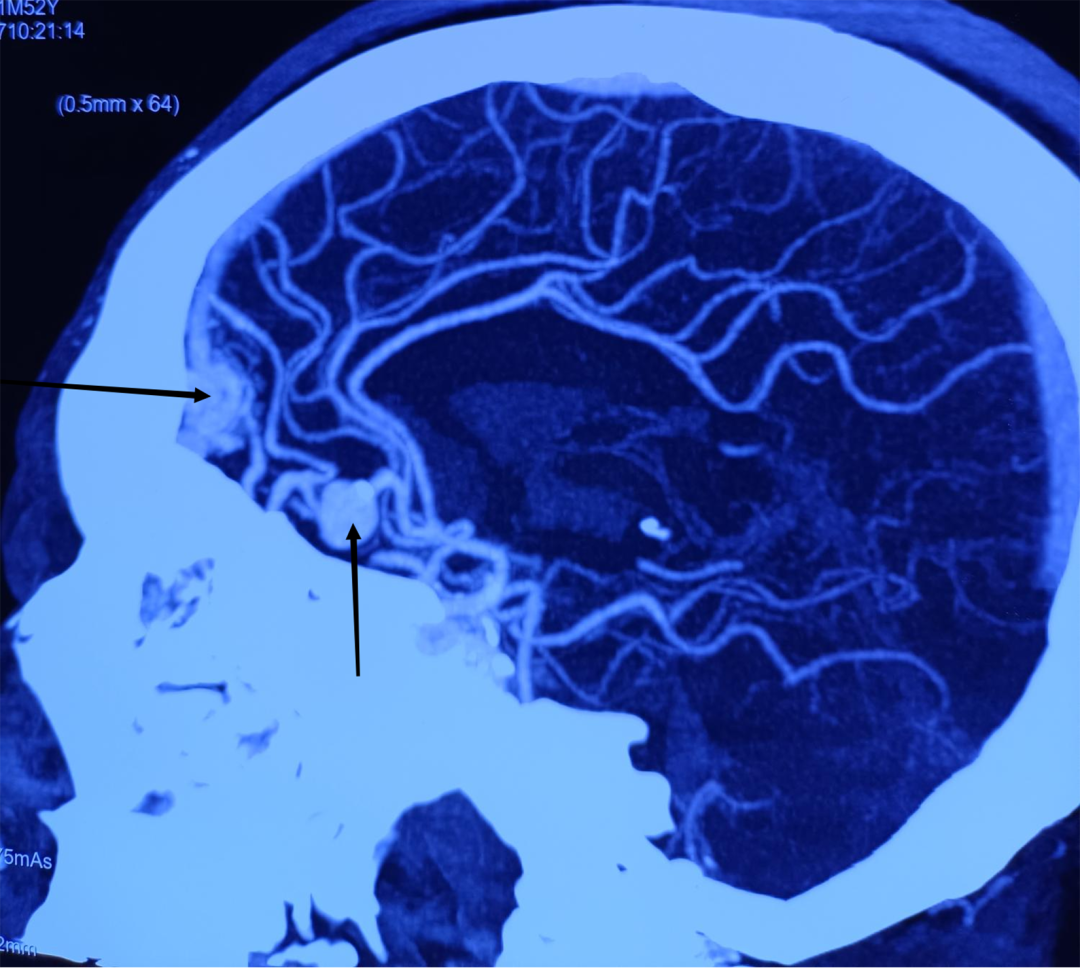

2022年10月27日,神经外科收住了一位“动脉瘤破裂出血”的危重患者。宫某入院时头痛、头晕、烦躁、意识模糊,双下肢无力。田垒医生接诊后立即给患者完善检查,立即向二线医师汇报患者情况。董永军副主任为患者查体,仔细查看头颈CTA和颅脑CT,在北医三院神经外科驻延专家张嘉教授和田德洲主任的指导下,对患者的身体状况进行了综合评估,考虑为脑动脉瘤合并动静脉畸形。面对如此凶险的病情,必须准确而快速地进行治疗。时间就是生命,决定立即为宫某实施全脑血管造影术+左侧大脑前动脉A2段动脉瘤介入栓塞术,防止动脉瘤二次破裂。

在介入科和麻醉手术科医护人员的全力配合下,董永军副主任给患者做了全脑血管造影,确定了动脉瘤的大小和位置,然后输送释放弹簧圈,顺利栓塞破裂出血的动脉瘤,经过2小时的“奋战”,手术顺利完成。考虑到患术前意识不清及脑血管疾病的潜在风险,转入重症监护室观察治疗。术后第二天患者清醒,言语、四肢活动基本正常,转入普通病房行腰大池引流。术后第三天患者再次意识不清、烦躁,复查颅脑CT显示:急性梗阻性脑积水,急诊行侧脑室穿刺引流术,手术历经20分钟,手术顺利。二次术后第二天,患者意识清楚,言语、运动功能正常、饮食均可。术后第6天,患者开始尿量增加,淡漠。尿量达7000ml每天,血钠降至112mmol/L。结合化验结果及临床表现,考虑发生了尿崩症。给与补充电解质,口服去氨加压素片、双克等治疗后尿量逐渐恢复正常,电解质也随之恢复正常。现患者症状基本消失,顺利出院。

董永军副主任介绍:动脉瘤是一种高死亡率的疾病,多为发生在颅内动脉管壁上的异常膨出,是造成蛛网膜下腔出血的首要病因,这类疾病的发生往往会导致患者的病情迅速加重导致死亡。一旦发现颅内动脉瘤,应该充分评估破裂风险,破裂风险较高者建议介入治疗或者开颅夹闭治疗。相较于以往的传统开颅手术,介入栓塞只需动脉穿刺一个小口,无需开颅,创伤小,缩短了手术时间和住院日程,降低并发症发生率,术后恢复快。